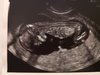

Maluch prawie 7cm wg usg 13+1 więc trochę starsza ciąża :)

Serducho bije 168/min, kości nosowe prawidłowe przeziernosci 1.1 więc wszystko w jak najlepszym porządku... Następna wizyta 4.01.2019 więc już wtedy doktorek obiecał powiedzieć płeć bo dzisiaj widział ale mówi że woli upewnić się i jak będzie pewny to mi powie...

Jeju jaka ja jestem szczęśliwa :) :) :)